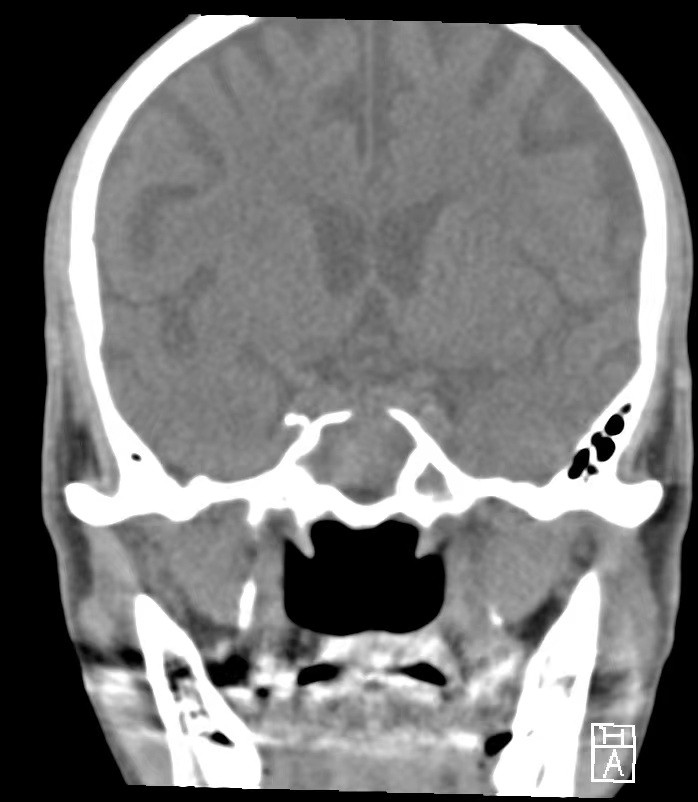

5月11日,一名92岁的老人因反复发作头痛入住哈医大一院耳鼻喉科二病房,经耳鼻喉科二病房张小鹏副主任医师检查,诊断为真菌性蝶窦炎。考虑患者头痛剧烈,已影响正常生活,现患者颅底骨质已经破坏,如不尽早处理,真菌进一步侵犯到颅内,将使患者生命受到威胁。耳鼻喉科二病房张天虹教授组织麻醉科、神经外科、心内科、呼吸科等科室综合评估,决定给予患者全麻鼻内镜下鼻窦炎手术治疗。

张小鹏副主任医师介绍,患者的病变位于鼻部的最深方的蝶窦内,起病比较隐匿、病程较长。蝶窦周围有颅底,颈内动脉,视神经等重要结构,患者高龄,抗打击能力弱,如损伤将造成颅内感染,大出血,失明等严重并发症,所以手术一定要在不造成严重并发症的情况下快速精准的完成。

5月12日,在麻醉医师的配合下,耳鼻喉科二病房张小鹏副主任医师以熟练的技术在内镜下为患者开放了双侧筛窦及蝶窦,彻底清除了病灶,成功的完成这台手术。手术仅用时30分钟。术后6小时,老人已能正常进食、活动,无明显的疼痛不适。手术24小时后便顺利出院。